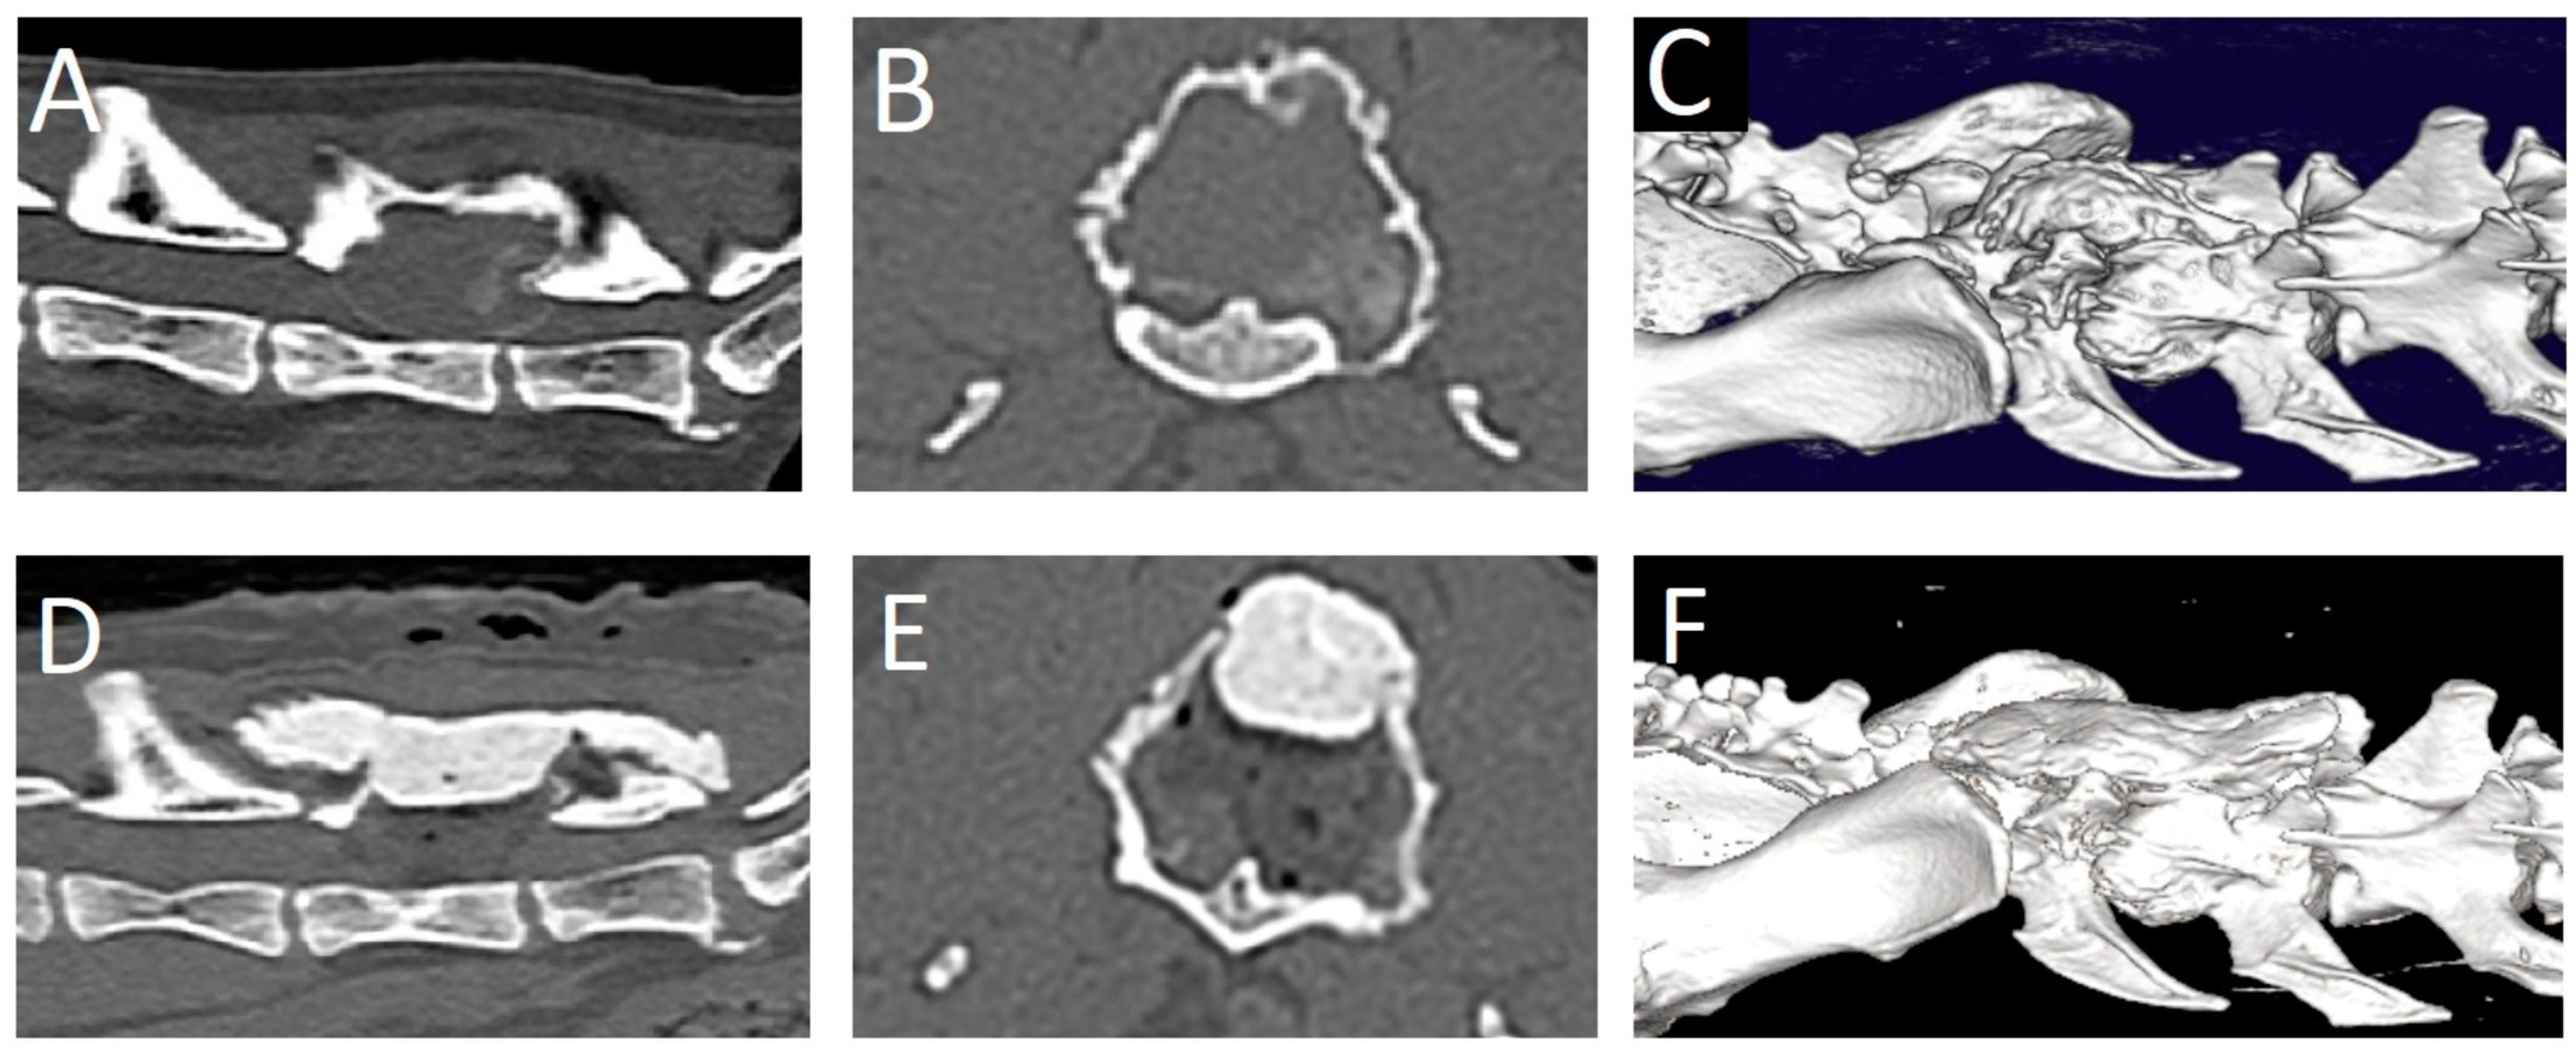

A 15.5-year-old male neutered domestic shorthaired cat was presented for chronic progressive lameness of the right pelvic limb over the last 4 months. During the last 2 weeks, the signs had progressed with the involvement of the left pelvic limb as well. The referring veterinarian had prescribed meloxicam (0.05 mg/kg q24h per os). However, a significant improvement was not achieved. During a follow-up neurological evaluation, proprioceptive deficits and spinal hyperesthesia were noted. Orthogonal radiographs of the lumbar vertebral column revealed a right-sided osteolytic mass lesion affecting the L6 vertebra (Figure 3). Gabapentin (10 mg/kg q12h) was added to the treatment and a CT scan was performed. The CT revealed a large (2.2 × 2.0 × 2.9 cm), expansile mass lesion in the dorsal lamina of the L6 vertebra (Figure 4). The mass also infiltrated the pedicles bilaterally (right more than left). The mass showed soft tissue attenuation centrally and a thin, mineralized peripheral rim. Its borders were mildly irregular and quite well defined. There was severe stenosis of the spinal canal, mainly at the level of the caudal part of L6. Caudally, the mass extended dorsally to L7. It did not appear to affect any part of the L7 vertebra. The soft tissue attenuating portion showed diffuse contrast enhancement. Differential diagnoses based on the CT findings mainly included a primary bone tumor such as fibrosarcoma, osteosarcoma, or chondrosarcoma. A fine-needle aspiration biopsy of the mass was attempted, but the acquired sample was non-diagnostic. Surgical treatment was planned. The dosage of gabapentin was increased (10 mg/kg q8h), and meloxicam was discontinued and replaced with prednisolone (1 mg/kg q24h) 2 weeks before surgery.

A dorsal midline skin incision was performed from L4 to S1. The fascia was bilaterally incised on the midline dorsal to L5-L7. The epaxial muscles were elevated from the spinous processes with a periosteal elevator and retracted laterally on both sides. Hemostasis was achieved using bipolar electrocautery. The tumor was visualized. It had a very hard consistency on the outer aspect. The dorsal and right lateral parts of the tumor wall were removed using rongeurs. Thereafter, the soft content of the mass was removed by curettage. The compressive, thin external bony layer was easily removed using a curette and a Kerrison rongeur. The L6 spinal nerve on the left side was accidentally severed in the process. Decompression was achieved and deemed satisfactory based on the visualization of the spinal cord and nerve roots in the expected position in the spinal canal. A thin autologous free fat graft was placed to cover the laminectomy defect. A molded piece of polymethylmethacrylate (PMMA) was placed dorsally to L5-sacrum to replace the removed dorsal lamina and cover the spinal canal. Monofilament absorbable suture materials were used to close the fascia, subcutis, and skin (intradermal). Decompression was evaluated as satisfactory on post-operative CT images (Figure 4). Post-operative care consisted of urinary bladder catheterization, ketamine (5 ug/kg/h) for 24 h, prednisolone (1 mg/kg q24h for 2 weeks, tapering scheme thereafter over the next 2 months), and gabapentin (10 mg/kg q8h for 3 weeks). One day post-surgery, the cat was ambulatory paraparetic. Improvement in neurological function was noted over the next 3 months post-surgery, at which point no residual signs were noticed by the owner.

Figure 4. Computed tomography images of case 2. Pre-operative: (A): sagittal plane, (B): transverse plane, (C): 3D reconstruction. Note the irregular, lobulated mass with soft tissue attenuation in the center and a mineralized outer rim. There is severe stenosis of the spinal canal due to the mass. Post-operative: (D): sagittal plane, (E): transverse plane, (F): 3D reconstruction.